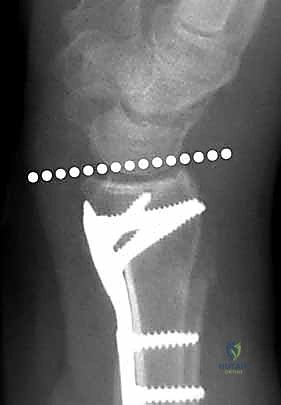

يعتمد الدكتور محمد هطيف على أحدث التقنيات التشخيصية، حيث يبدأ بـ الأشعة السينية (X-rays) في وضعيات متعددة. وفي حالات الكسور المعقدة التي تمتد إلى داخل المفصل، يتم إجراء تصوير مقطعي محوسب (CT Scan) لبناء صورة ثلاثية الأبعاد للكسر، مما يساعد في التخطيط الجراحي الدقيق.

4. وضع الصفيحة والتثبيت المؤقت

يتم اختيار صفيحة تيتانيوم مصممة تشريحياً لتلائم انحناء الكعبرة. توضع الصفيحة على العظم وتُثبت مؤقتاً بأسلاك معدنية دقيقة (K-wires).

5. حفر العظم ووضع المسامير

يتم حفر ثقوب في العظم عبر فتحات الصفيحة، ثم تُقاس المسافات بدقة لإدخال مسامير القفل (Locking Screws) في الجزء البعيد (قرب المفصل) ومسامير قشرية في الجزء القريب (في ساق العظم).

6. الفحص النهائي والإغلاق

يتم إجراء فحص أخير بالأشعة للتأكد من المحاذاة المثالية للكسر وأطوال المسامير (لضمان عدم بروزها واحتكاكها بالأوتار الخلفية). بعد ذلك، يتم خياطة الأنسجة والجلد بخيوط تجميلية ووضع ضمادة معقمة.